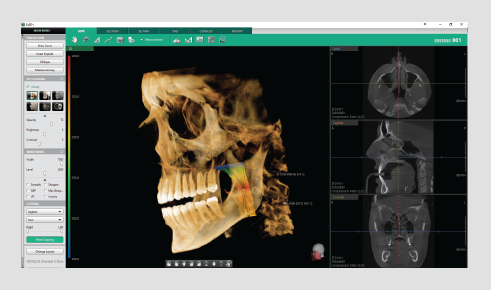

Powered by a new 3D VR graphics engine, the Ez3D-i is the ideal tool to effortlessly obtain the correct perspectives needed for accurate and true-to-measurement diagnosis.

• Various VR coloring modes and 2D filters

• Intuitive implant simulation tools for collision detection (implant/canal), bone density verification, and oblique viewing tools

• 3D panoramic navigation

Quickly and easily switch between multiple VR views